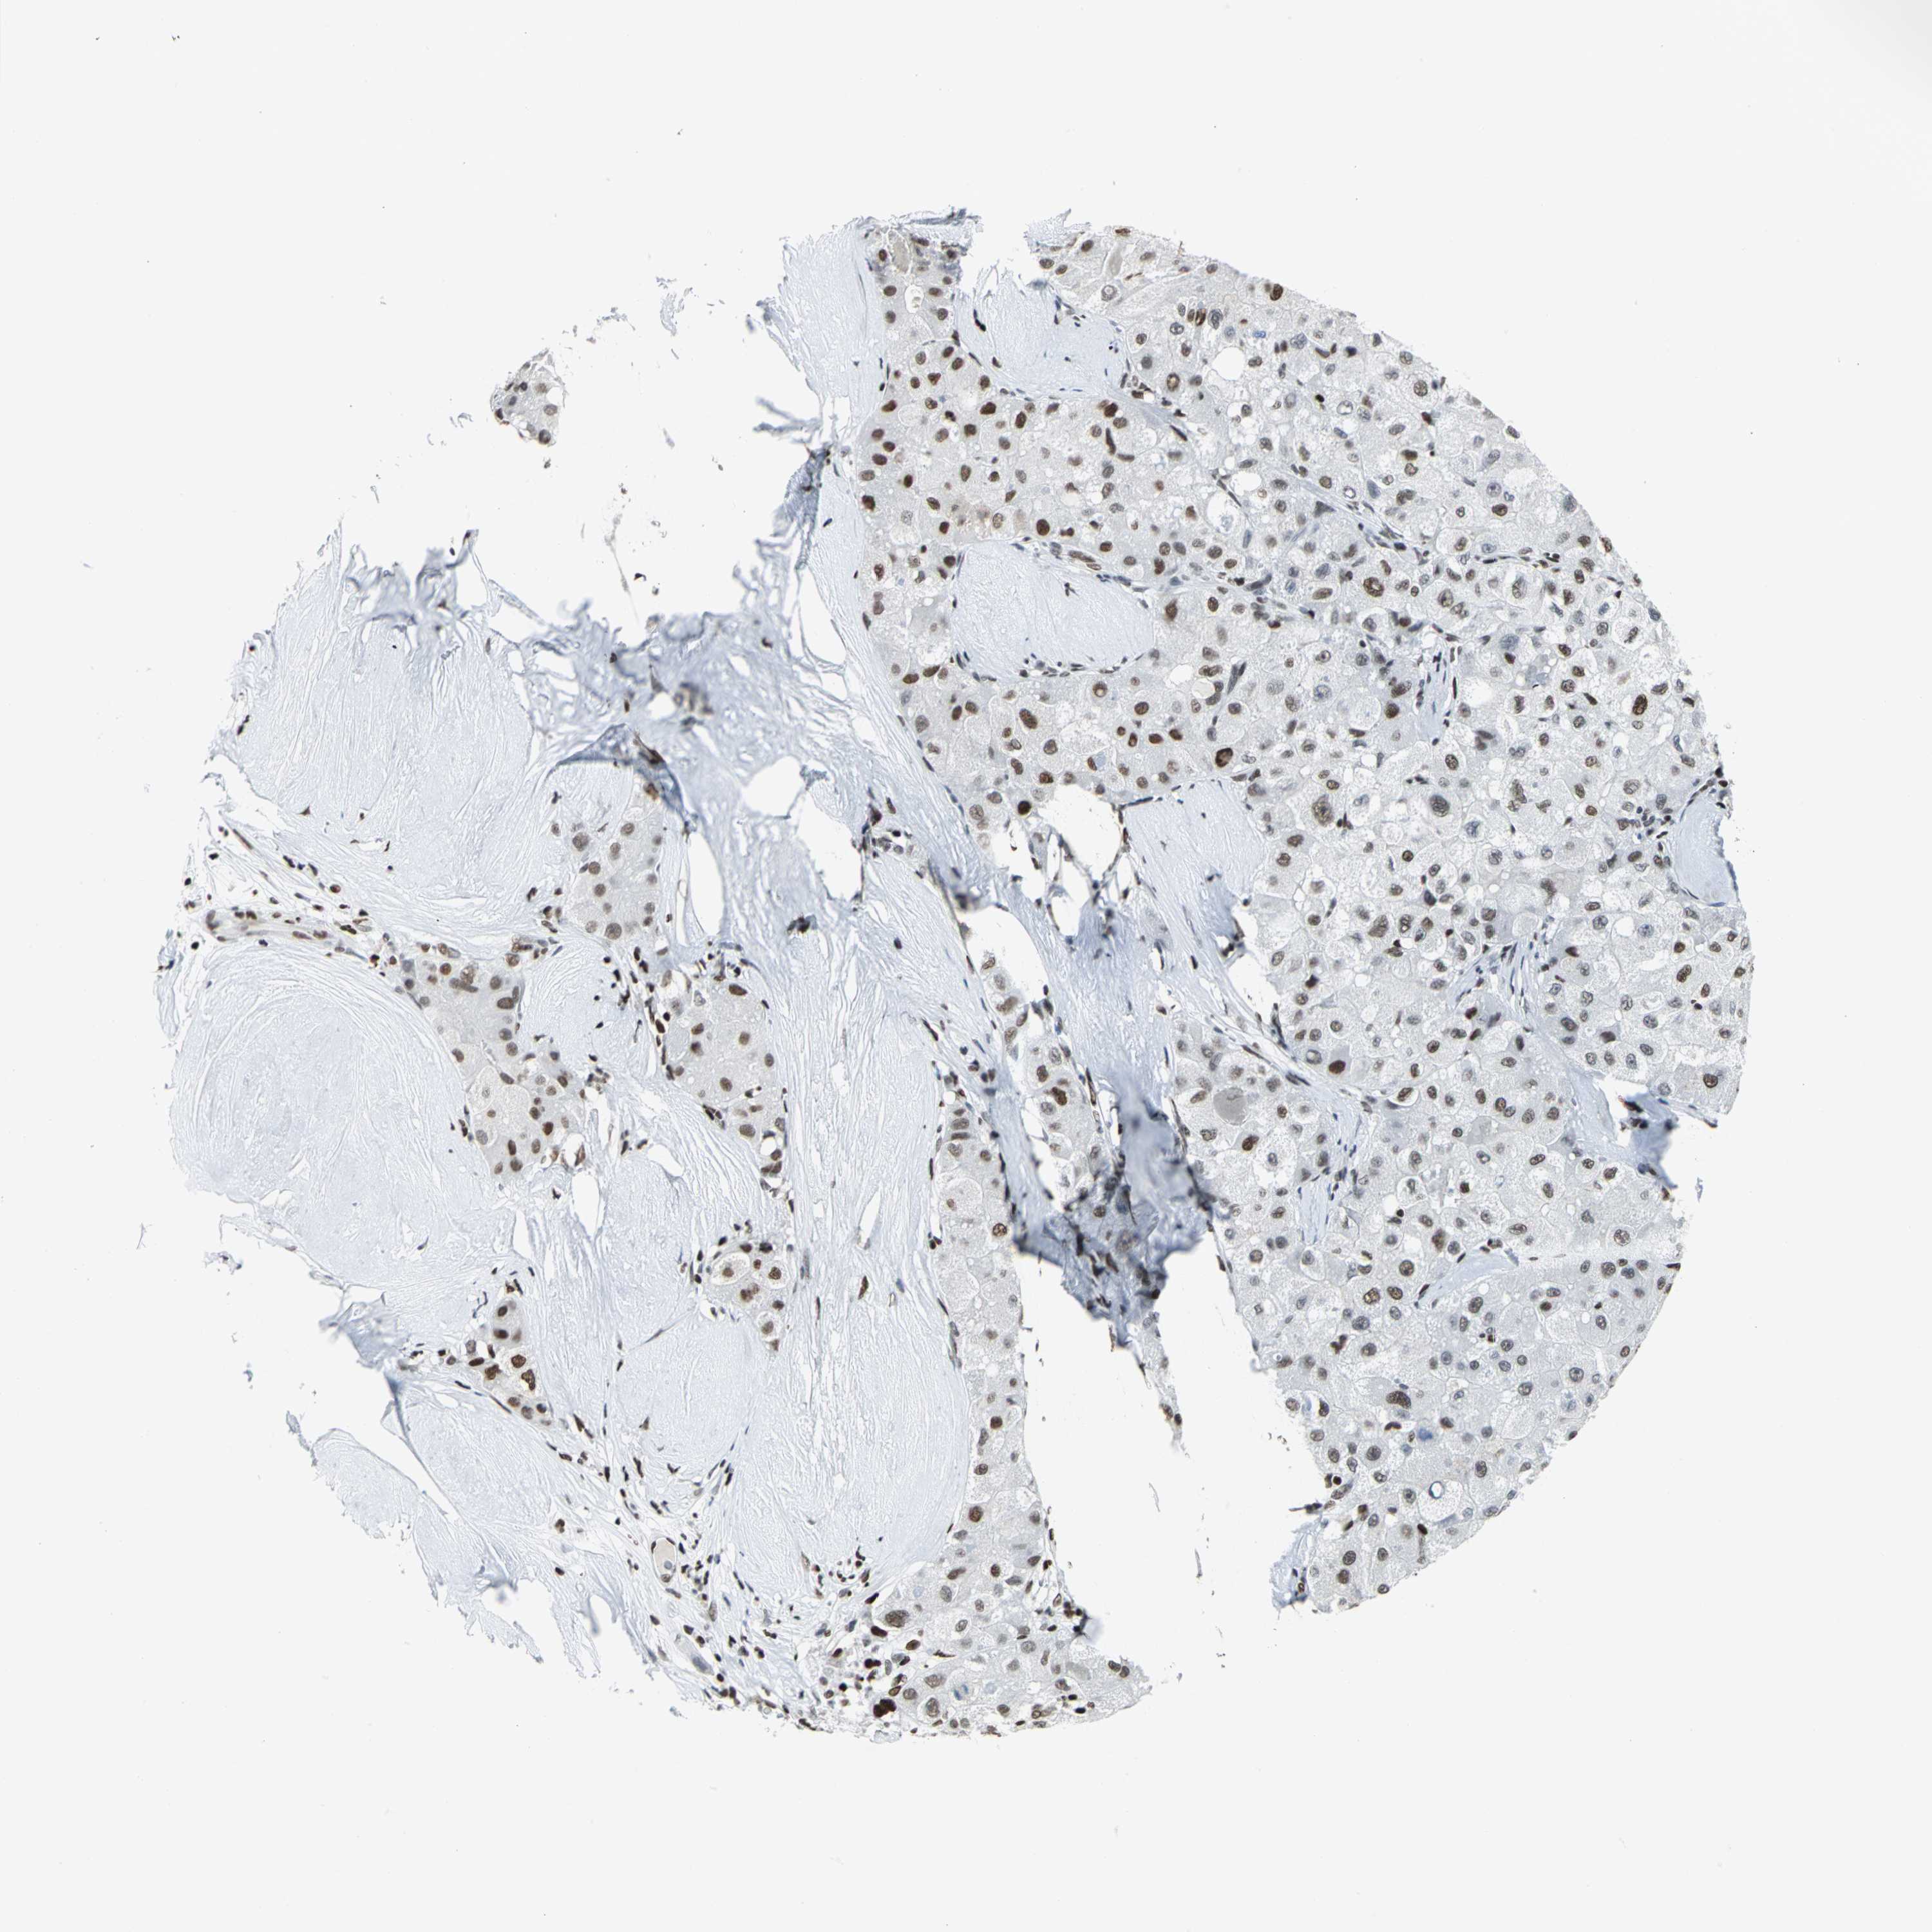

LIVER CANCER - Protein expressioni

A mouse-over function shows sample information and annotation data. Click on an image to view it in a full screen mode. Samples can be filtered based on level of antibody staining by selecting one or several of the following categories: high, medium, low and not detected. The assay and annotation is described here.

Note that samples used for immunohistochemistry by the Human Protein Atlas do not correspond to samples in the TCGA dataset.

Antibody stainingi

Antibody staining in the annotated cell types in the current human tissue is reported as not detected, low, medium, or high, based on conventional immunohistochemistry profiling in selected tissues. This score is based on the combination of the staining intensity and fraction of stained cells.

Each image is clickable and will lead to virtual microscopy that enables deeper exploration of all samples and also displays staining intensity scores, fraction scores and subcellular localization as well as patient and tissue information for each sample.

Antibody HPA004911

Staining

High

Medium

Low

Not detected

Intensity

Strong

Moderate

Weak

Negative

Quantity

>75%

75%-25%

<25%

None

Location

Nuclear

Cytoplasmic/membranous

Cytoplasmic/membranous,nuclear

Cholangiocarcinoma

Carcinoma, Hepatocellular, NOS